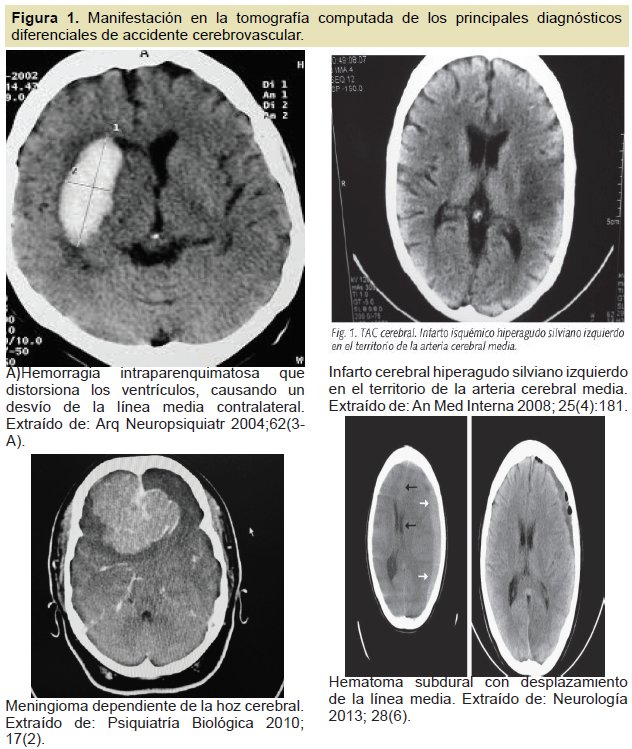

En nuestro estudio no se reportó ningún caso. Parece ser que las recomendaciones de medición de la glicemia en pacientes que presenten esta sintomatología, especialmente adultos mayores, han sido bien asimiladas por el personal de atención primaria19. En la Figura 1 se presentan los principales diagnósticos diferenciales de los accidentes cerebrovascular y su manifestación en la tomografía computada.